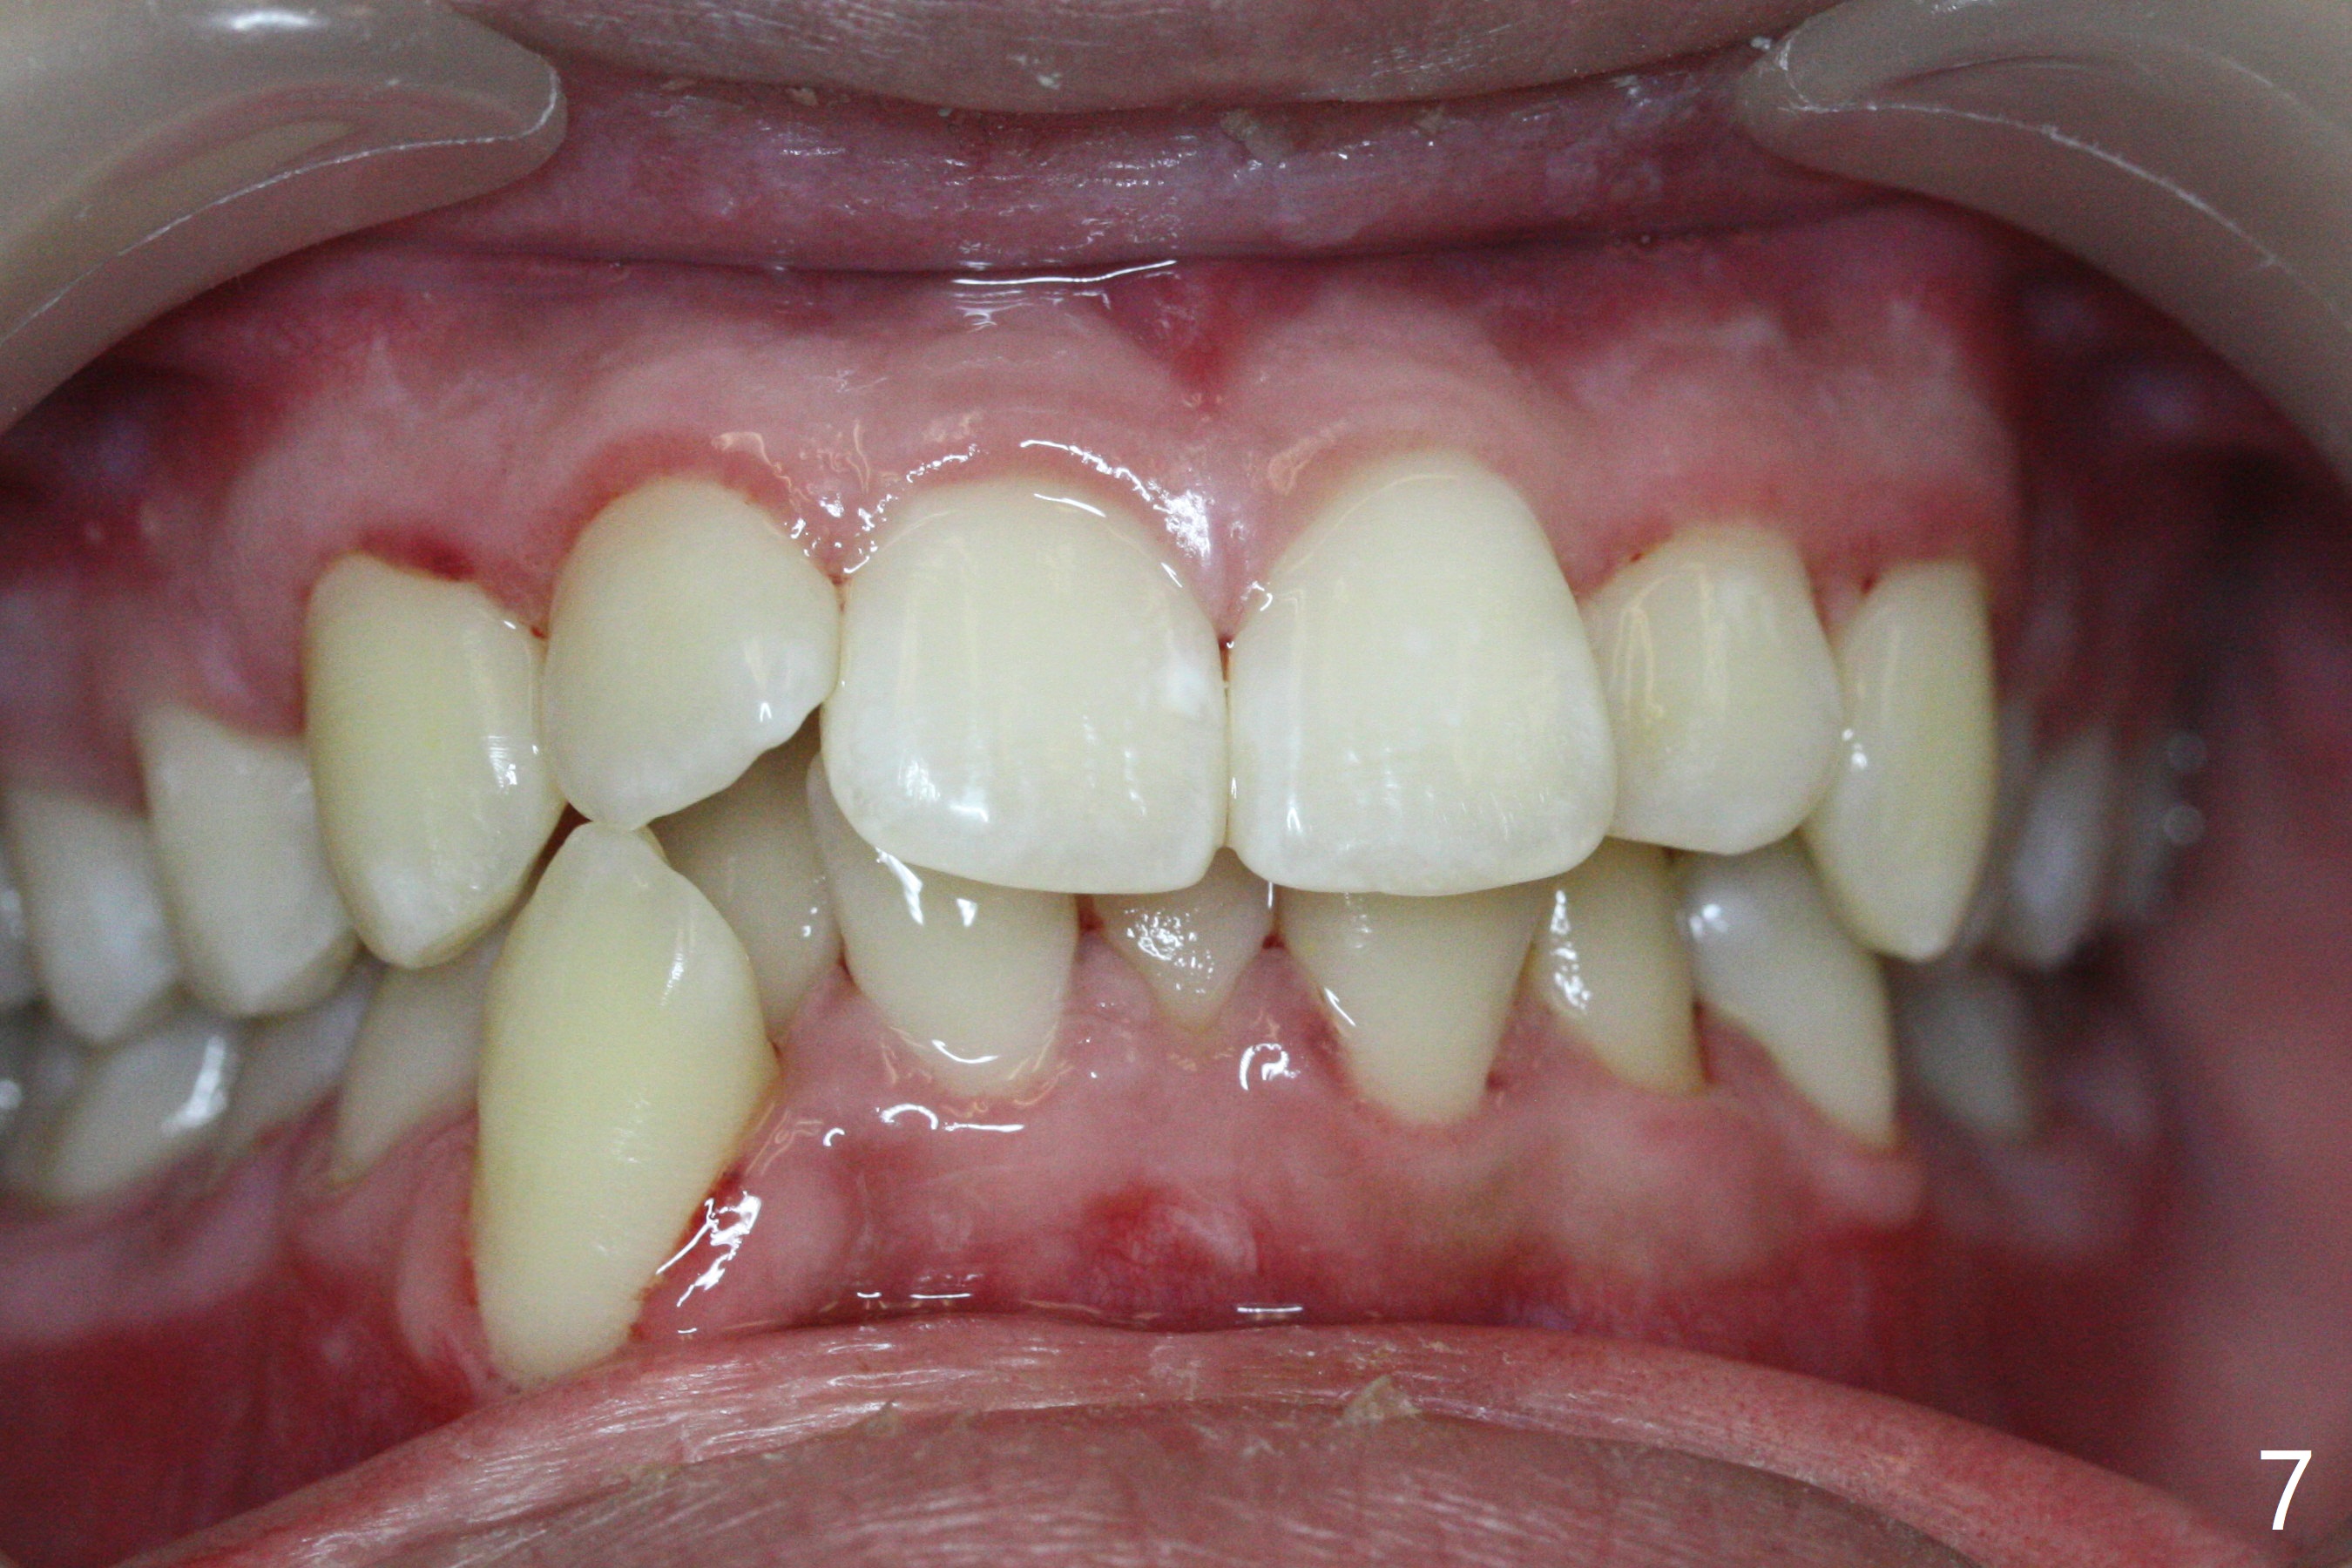

A 15-year-old man requests orthodontic treatment and agrees with extraction.  It appears that the maxilla is more protrusive than the mandible (Fig.1-4, 6,8).  The lower right canine has severe gingival recession (Fig.6,7,10).  Can we extract U4s and LR3 or 2 instead, considering relatively normal alignment in LL (Fig.8, occlusal view)?